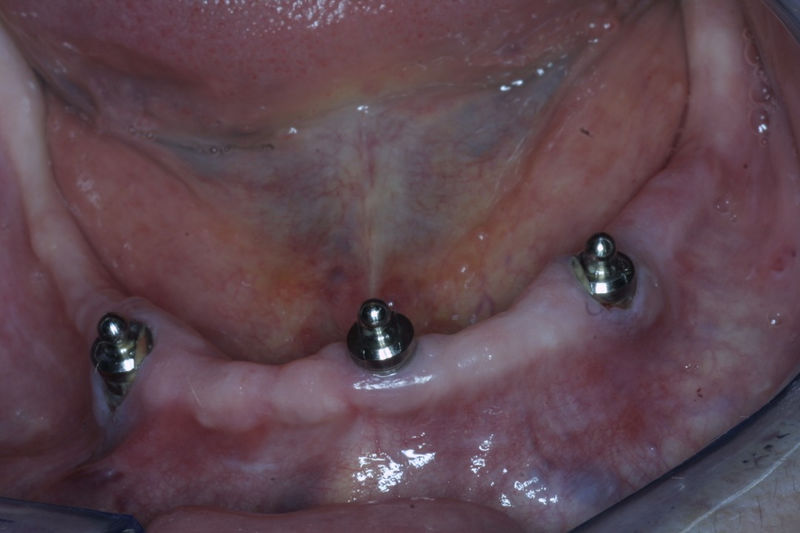

Son estructuras de titanio las cuales se colocan en el hueso y se utilizan para soportar coronas, prótesis fijas, removibles y totales. La colocación de los implantes se hacen previo análisis tomográfico.

Restauraciones fabricadas en el laboratorio los cuales se usan para reemplazar dientes ausentes en toda una arcada usando implantes y/o tejidos blandos como soporte y que pueden y deben de ser removidas para su limpieza. Para poder enviar el caso al laboratorio se toman impresiones utilizando materiales de impresión o técnicas modernas digitales.